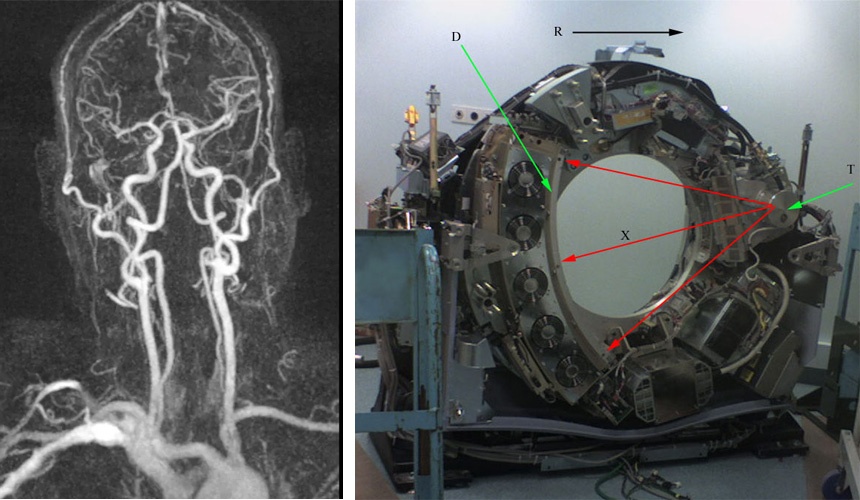

Компьютерная томография – довольно неточный термин, вводящий в заблуждение. Фактически это – продвинутая рентгеновская съемка. Специальная кольцевая форма блока излучателя-детекторов позволяет вращать всю конструкцию вокруг пациента и вести последовательную послойную съемку. КТ в исследовании мозга годится в основном для определения черепно-мозговых травм и кровотечений, а также ангиографии с контрастным веществом, так как ткани мозга слишком однородны и проницаемы для рентгеновских лучей по сравнению, к примеру, с костной тканью.

Компьютерную обработку КТ-изображений можно применить для получения объемной реконструкции той или иной части тела. Такая объемная визуализация может быть очень полезной для разработки тактики лечения или хирургического вмешательства. Вместе с реконструкцией черепа в 3D может быть также представлена ангиографическая картина, положение протезируемых участков кости и т.д.

В результате получаются снимки, настолько до боли всем известные по медиа, что их можно даже не приводить. Но стоит привести ссылку на различные виды визуализации с помощью МРТ. МРТ также позволяет делать ангиографию, только контрастом у нее будут не рентген-поглощающие, а, как нетрудно догадаться, парамагнитные вещества. Кроме того, МРТ позволяет делать самые настоящие видео, например, работы клапанов бьющегося сердца.